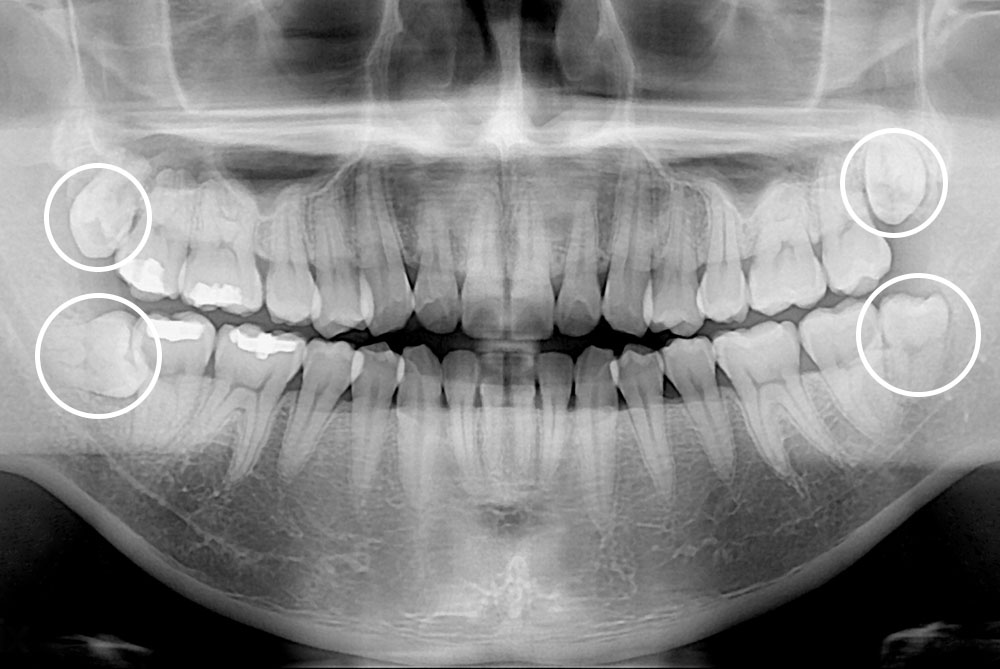

[사랑니] 매복 사랑니 발치

치료전 : 2018-10-15